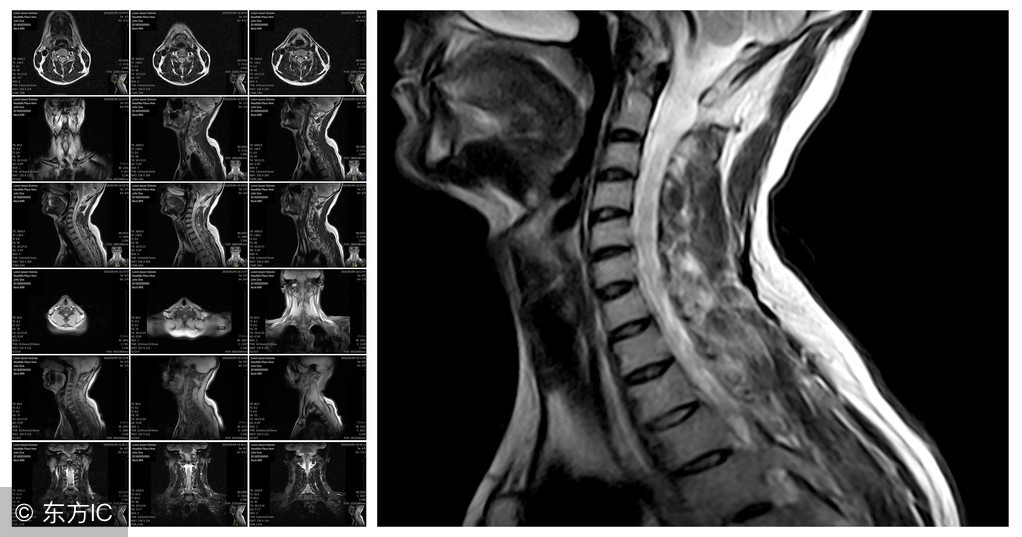

颈椎间盘突出症的起病原因主要是由于颈椎间盘的退行性变,其中包括髓核的膨隆、突出及脱出,均表示颈椎病的不同阶段。但是在临床上常可遇到突发性颈椎间盘突(脱)出症,而且大多数是以瘫痪为首发症状。早于1978年开始,专家研究X线动力性侧位片上的梯形变及其他临床症状判定,并早期手术摘除髓核而取得满意疗效。此种类型者我们称之为“急性颈椎间盘突(脱)出症”。近年来MRI检查的开展,本病已为大家所证实。

其临床表现主要视受压迫的组织而定。从病理解剖角度来看,本病可分为以下两种类型:中央型及侧方型(图1)。

以前认为此型突出较少见,随着诊断技术的发展,特别是MRI技术问世之后,中央型颈椎间盘突出症已不再少见。